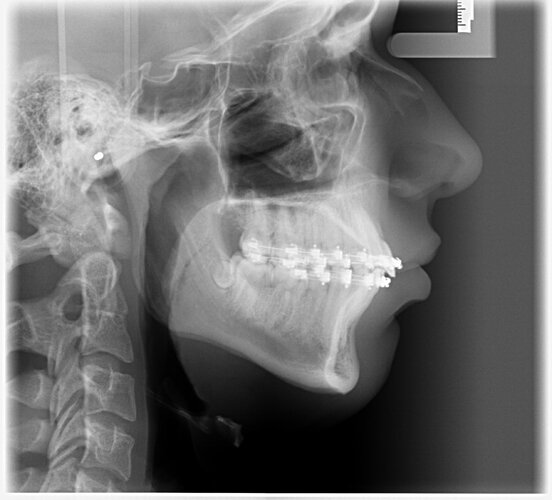

I had Bimaxsurgery + genioplasty yesterday performed by Dr Dr Kater, Frankfurt am Main, Germany. I'm 17 and it went well, no nerves are botched and he told me the Plan was executed perfectly fine. In the pictures you can see 24h before and 24h after the surgery. He did a great job with my maxilla and mandible but the genioplasty is slightly underadvanced. My nose had a very big glowup but it'll all look different in 5 months i'm very bloated rn. What do yall think?